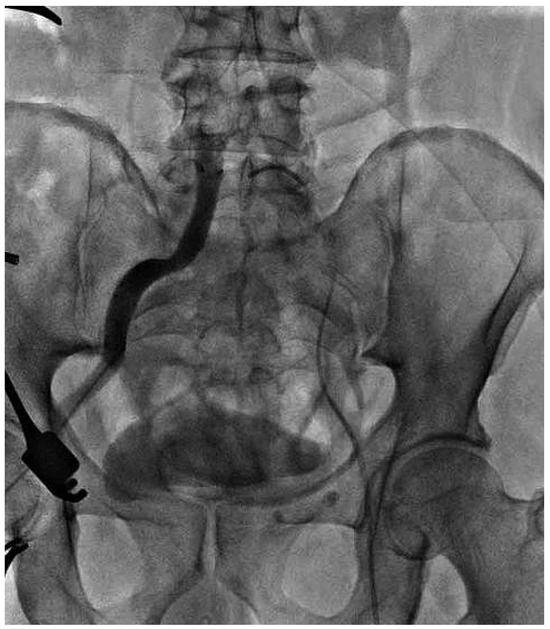

Endovascular Treatment of a Complex Type B Aortic Dissection

Case report